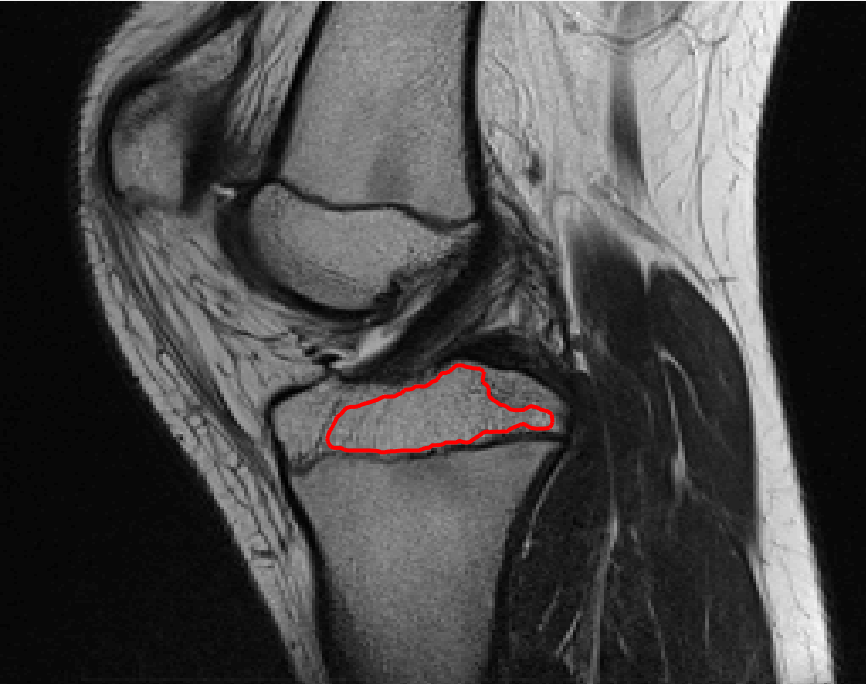

Four sets of test results are shown below. In Test 1 we compare models M1 – M6 to the proposed model M7 for two images which are hard to segment. The first is a CT scan from which we would like to segment the lower portion of the heart, the second is an MRI scan of a knee and we would like to segment the top of the Tibia. See Figure 9 for the test images and the marker sets used in the experiments. In Test 2 we will review the sensitivity of the proposed model to the main parameters. In Test 3 we will give several results achieved by the model using marker and anti-marker sets. In Test 4 we show the initialisation independence and marker independence of the Geodesic Model on real images.

Refer to captionRefer to captionRefer to captionRefer to caption

(i)                                 (ii)                                 (iii)                                 (iv)

Figure 9: Test 1 setting: (i) Image 1;  (ii) Image 1 with marker and anti-marker set shown in green and pink respectively;  (iii) Test Image 2; (iv) Image 2 with marker set shown.

Refer to caption

(a) M1 (Left to right:) Test Image 2 with markers (red) and anti-markers (blue), foreground segmentation and background segmentation (we used published software, no parameter choice required).

(b) M2 λ=1𝜆1\lambda=1, γ=15𝛾15\gamma=15.

(c) M3 λ=5𝜆5\lambda=5, θ=1𝜃1\theta=1.

(d) M4 λ=1/8𝜆18\lambda=1/8.

(e) M5 λ=1,γ=15,θ=110formulae-sequence𝜆1formulae-sequence𝛾15𝜃110\lambda=1,\gamma=15,\theta=\frac{1}{10}.

(f) M6 λ=15,θ=1formulae-sequence𝜆15𝜃1\lambda=15,\theta=1.

(g) M7 λ=10,θ=1formulae-sequence𝜆10𝜃1\lambda=10,\theta=1.

Figure 11: Visual comparison of M1 – M7 results for Test Image 2. M1 segmented part of the object, M2 – M4 failed to segment the object, M5, M6 and M7 correctly segmented the object.